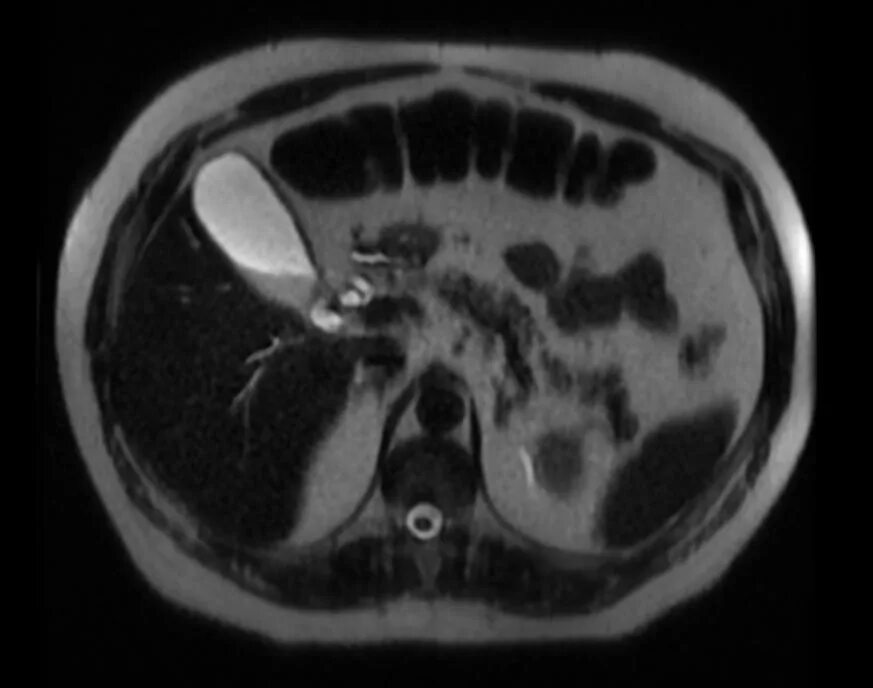

Седиментация в желчном